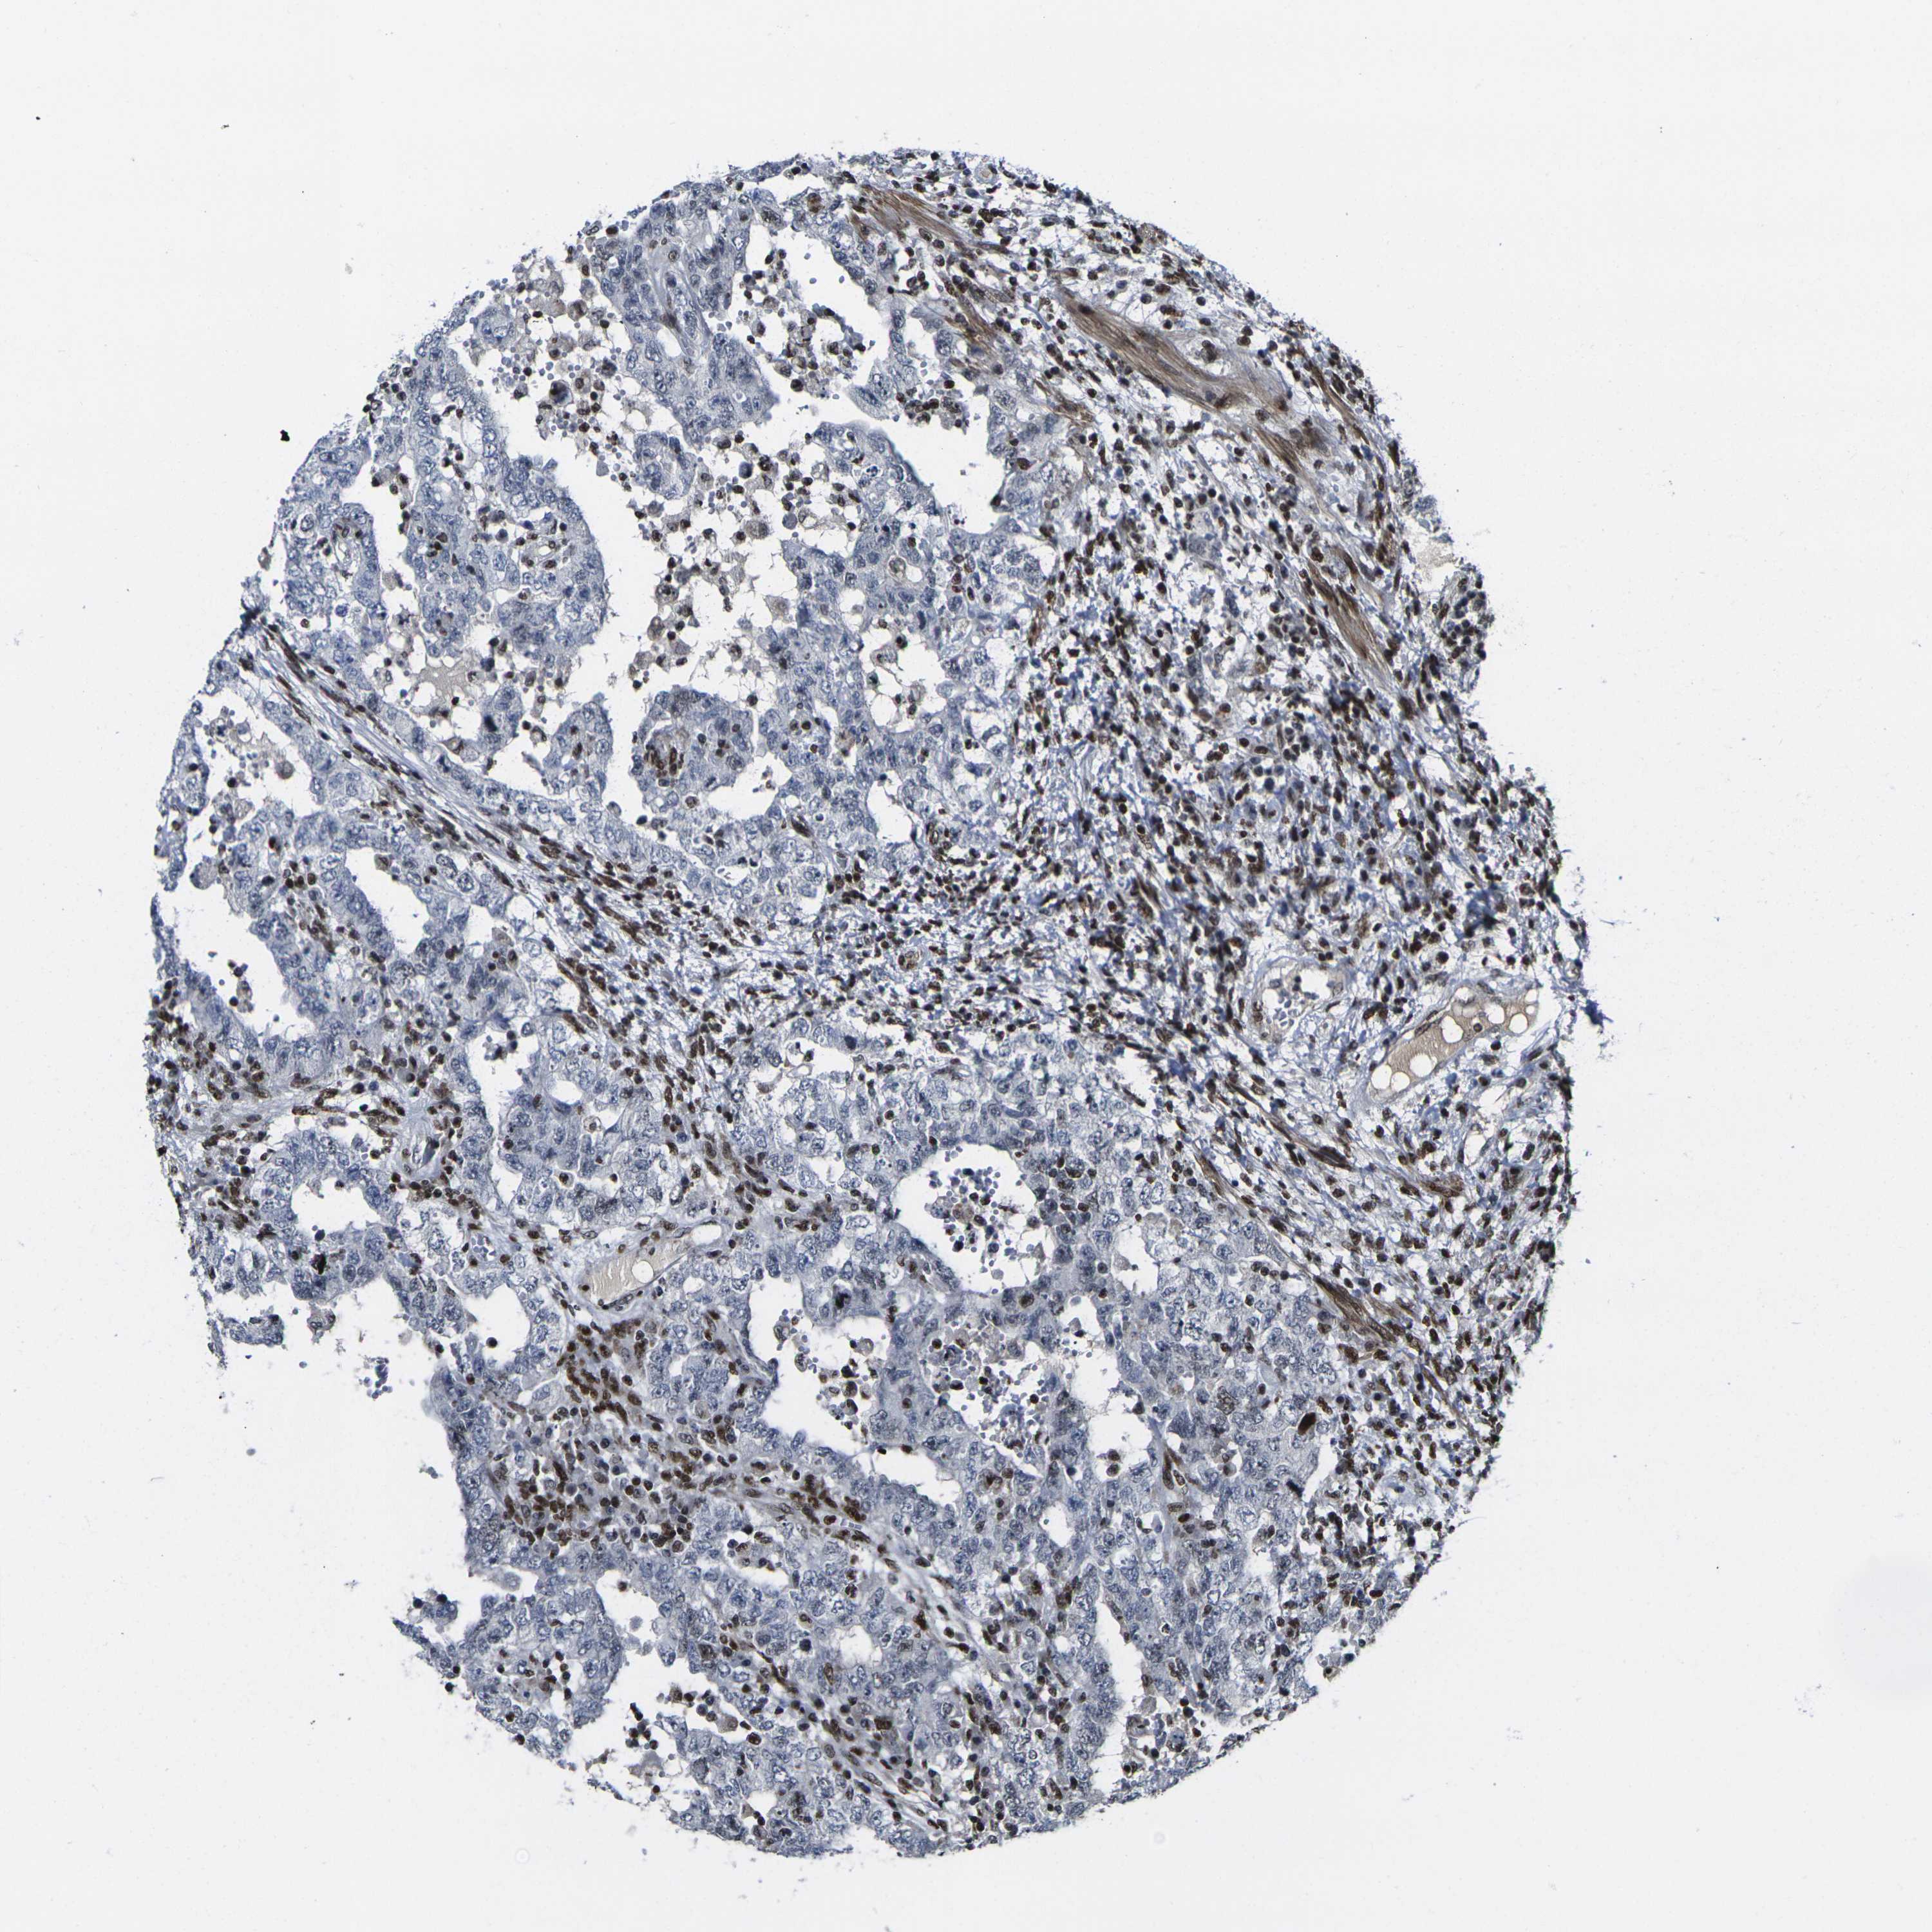

TESTIS CANCER - Protein expressioni

A mouse-over function shows sample information and annotation data. Click on an image to view it in a full screen mode. Samples can be filtered based on level of antibody staining by selecting one or several of the following categories: high, medium, low and not detected. The assay and annotation is described here.

Note that samples used for immunohistochemistry by the Human Protein Atlas do not correspond to samples in the TCGA dataset.

Antibody stainingi

Antibody staining in the annotated cell types in the current human tissue is reported as not detected, low, medium, or high, based on conventional immunohistochemistry profiling in selected tissues. This score is based on the combination of the staining intensity and fraction of stained cells.

Each image is clickable and will lead to virtual microscopy that enables deeper exploration of all samples and also displays staining intensity scores, fraction scores and subcellular localization as well as patient and tissue information for each sample.

Antibody HPA068431

Antibody CAB012235

Staining

High

Medium

Low

Not detected

Intensity

Strong

Moderate

Weak

Negative

Quantity

>75%

75%-25%

<25%

None

Location

Nuclear

Cytoplasmic/membranous

Cytoplasmic/membranous,nuclear

Seminoma, NOS

Carcinoma, Embryonal, NOS